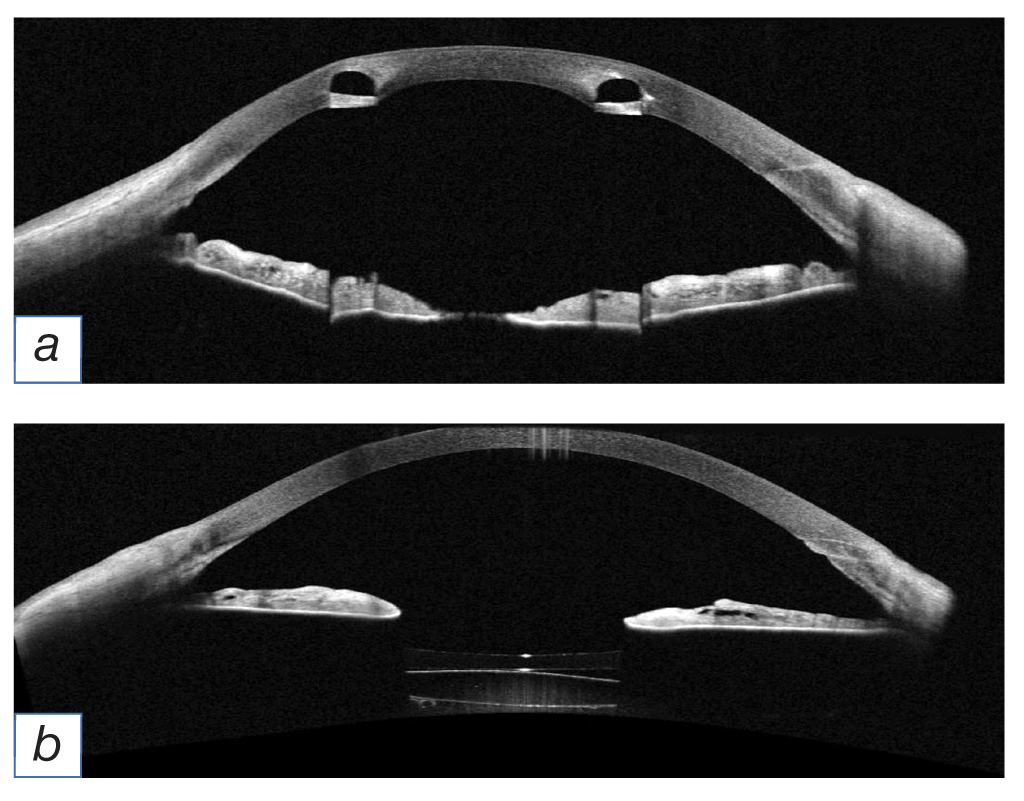

One month after surgery, the assessment and examination show that the cornea is transparent and smooth; the intrastromal corneal ring segments were clearly detected, the corneal incisions are sealed, the anterior chamber is deep, the iris is unremarkable, the aIOL is correctly positioned, just like the IOL in the posterior chamber. The vitreous body and the ocular fundus show no signs of abnormalities (Fig. 2).

Fig. 2. Optical coherent tomography of the left eye after surgical intervention: а — intrastromal corneal ring segment; b — the posterior chamber shows the presence of an additional intraocular lens and of the posterior chamber intraocular lens.